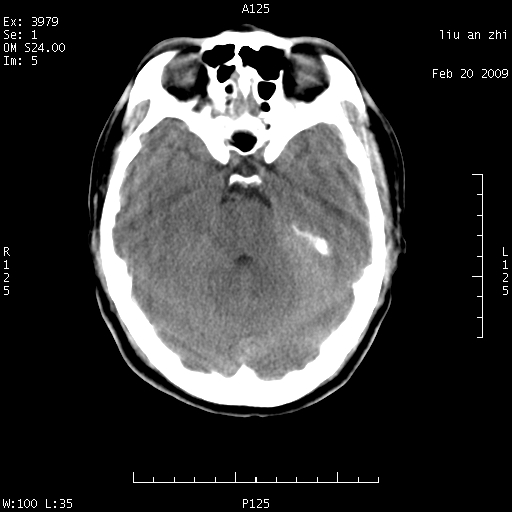

患者:男,32岁 被打伤后3天,自感头昏头痛作头颅ct检查。请大家看一下想什么??

请注意小脑幕!!!

考虑左侧天幕硬膜下血肿。

左侧天幕硬膜下血肿

ct18448的结果:mri检查左侧天幕下血肿

左侧小脑幕旁硬膜下出血。